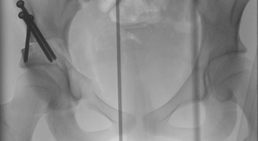

Beckenosteotomie bei Hüftdysplasie (Stellungskorrektur der Hüftpfanne), PAO (periazetabuläre Osteotomie)

Die Hüftdysplasie des Jugendlichen und Erwachsenen ist durch die in Österreich durch Prof. Reinhard Graf entwickelte Säuglingssonografie glücklicherweise...